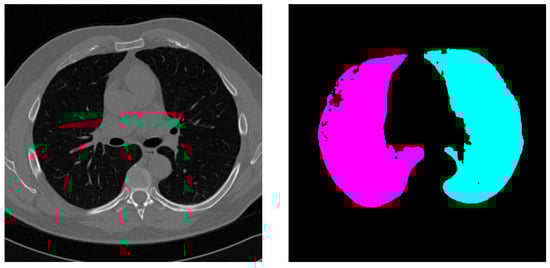

4.2. Qualitative Results

4.3. External Validation on PleThora Dataset